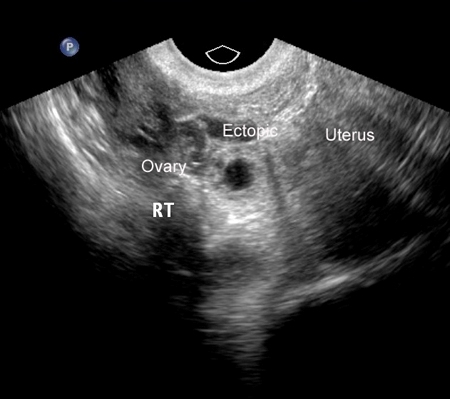

[Figure caption and citation for the preceding image starts]: Imagen de ultrasonido de embarazo ectópicoDe la colección de la Dra. Melissa Fries; usado con permiso [Citation ends].